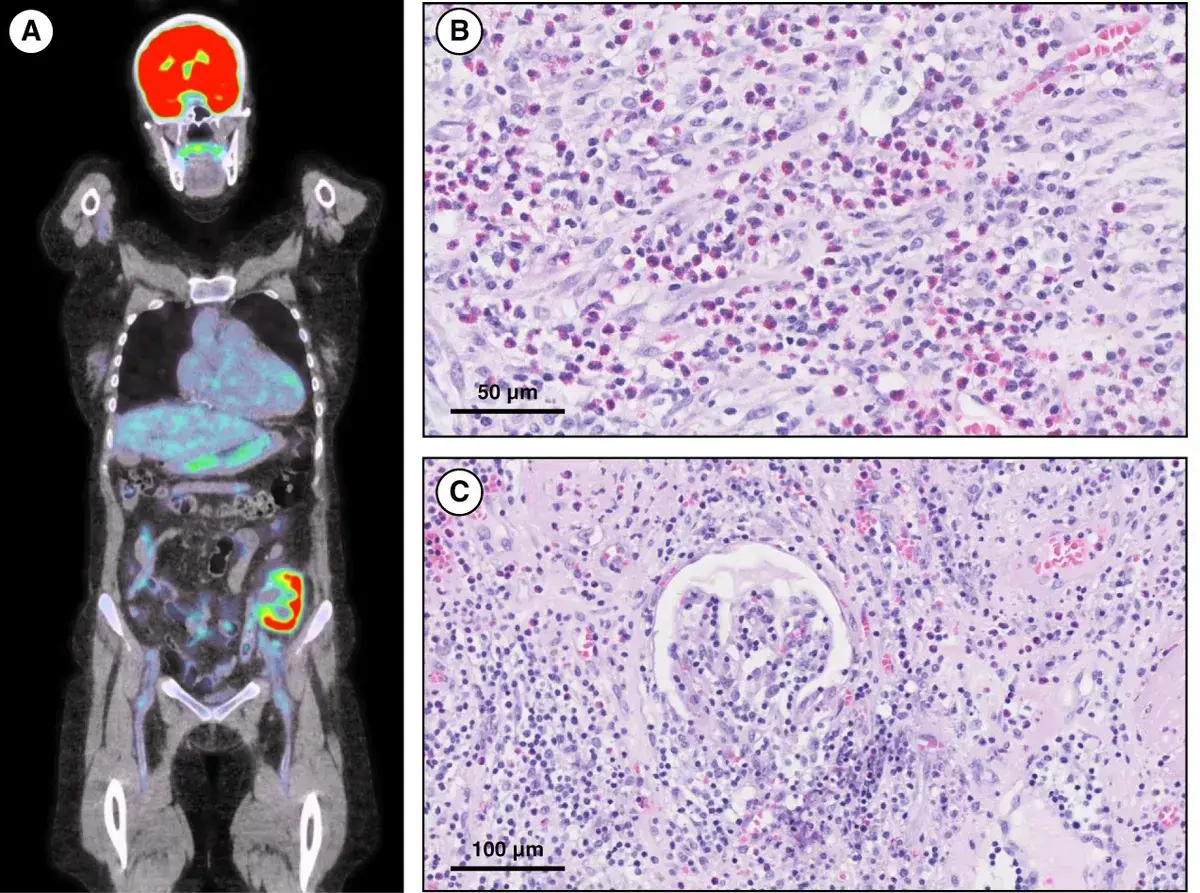

Hipercalcemia em DRC no pós-artroplastia: e se o vilão não for o PTH? Pistas discretas — 1,25(OH)₂D↑, ECA↑ e PET “quente” na prótese — apontam para ASIA por cimento ósseo. Acompanhe o raciocínio que faz o diagnóstico emergir e muda a conduta.

Valkercyo Feitosa

10 meses atrás